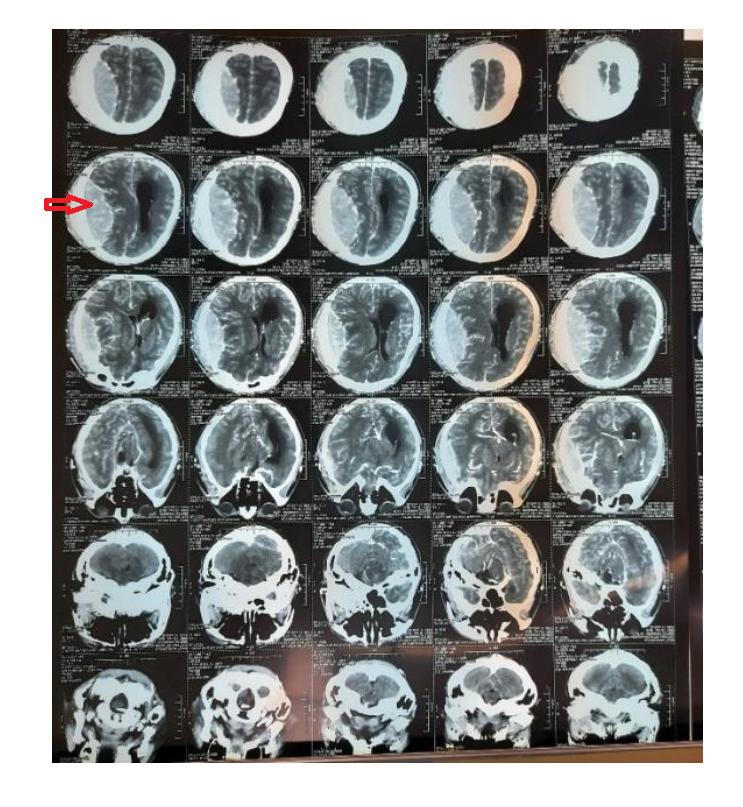

Hình ảnh u màng não trước phẫu thuật |

Kết quả chẩn đoán cho thấy bệnh nhân bị u màng não bán cầu (P) kích thước: 10 × 9 × 4cm, khối u gây tăng sinh xương, cơ thái dương và nhiều mạch máu, chèn ép nhu mô não, phù não nặng. Bệnh nhân được chỉ định phẫu thuật cấp cứu với phương pháp mở sọ và vi phẫu lấy trọn u.